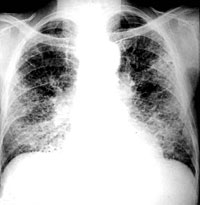

ESQUEMA 19 Comentario placa 19 En ambos pulmones se observa un compromiso difuso constituido por áreas irregulares de predominio periférico y basal que muestran elementos lineales de diferente grosor que forman un retículo irregular con escasa imágenes nodulillares poco definidas. La ocupación alveolar no permite distinguir en algunas zonas estos detalles. En el ángulo cardiofrénico derecho se esbozan algunos elementos areolares de panal de abejas. La TAC en estos casos aporta una mejor definición morfológica. Las posibilidades etiológicas son múltiples y es generalmente necesario considerar metódicamente los antecedentes clínicos y alteraciones funcionales e, incluso, llegar a la biopsia pulmonar para tener un diagnóstico seguro. Pase a la placa 20 |